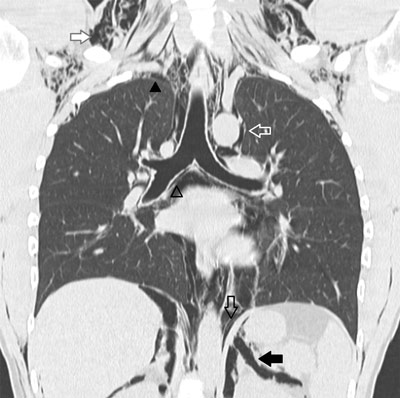

Figure C

CT of the chest confirming a pneumomediastinum (hollow black arrowhead, hollow black arrow and hollow white arrow) associated with diffuse subcutaneous emphysema (solid white arrow), pneumo(retro)peritoneum (solid black arrow) and pneumothorax (solid black arrowhead).